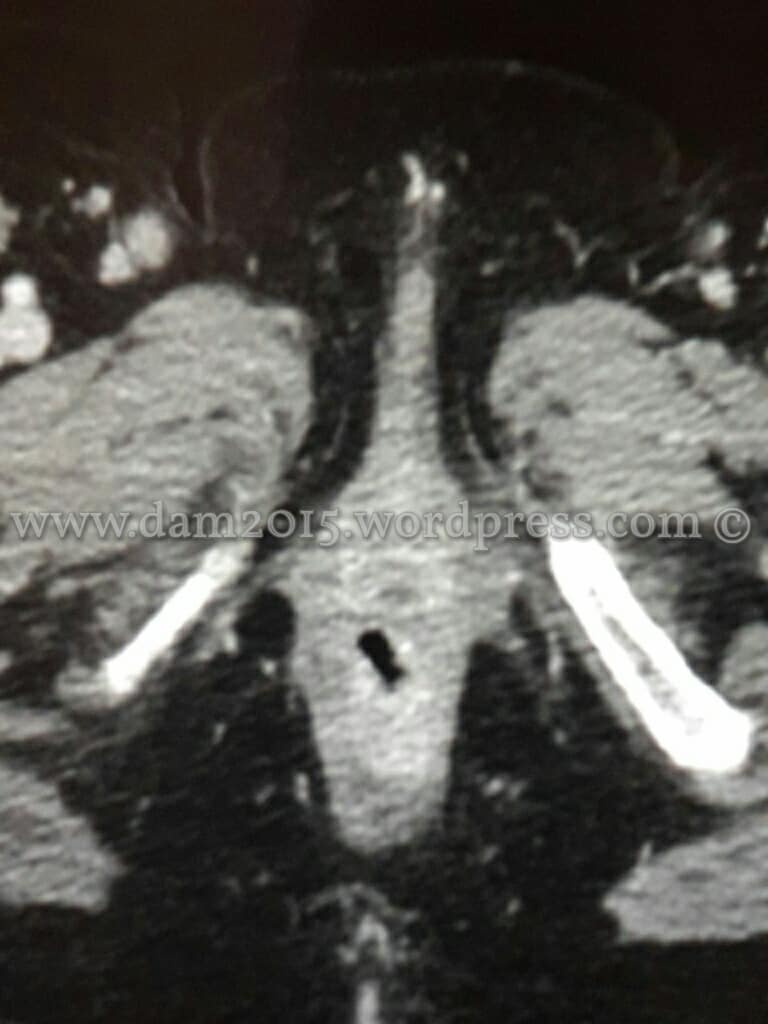

Si esegue TC torace e addome con MDC: in corrispondenza dell’ano si apprezza tessuto solido, che presenta intenso e precoce contrast-enhancement dopo somministrazione di MDC che si estende dal margine anale esterno fino al retto basso. Tale struttura interessa cute e sottocute e presenta estensione assiale massima di circa 97x40mm ed estensione cranio-caudale di circa 70mm. Presenza di multipli linfonodi di dimensioni aumentate in sede inguinale, otturatoria, iliaca, lomboaortica e lungo il mesentere.